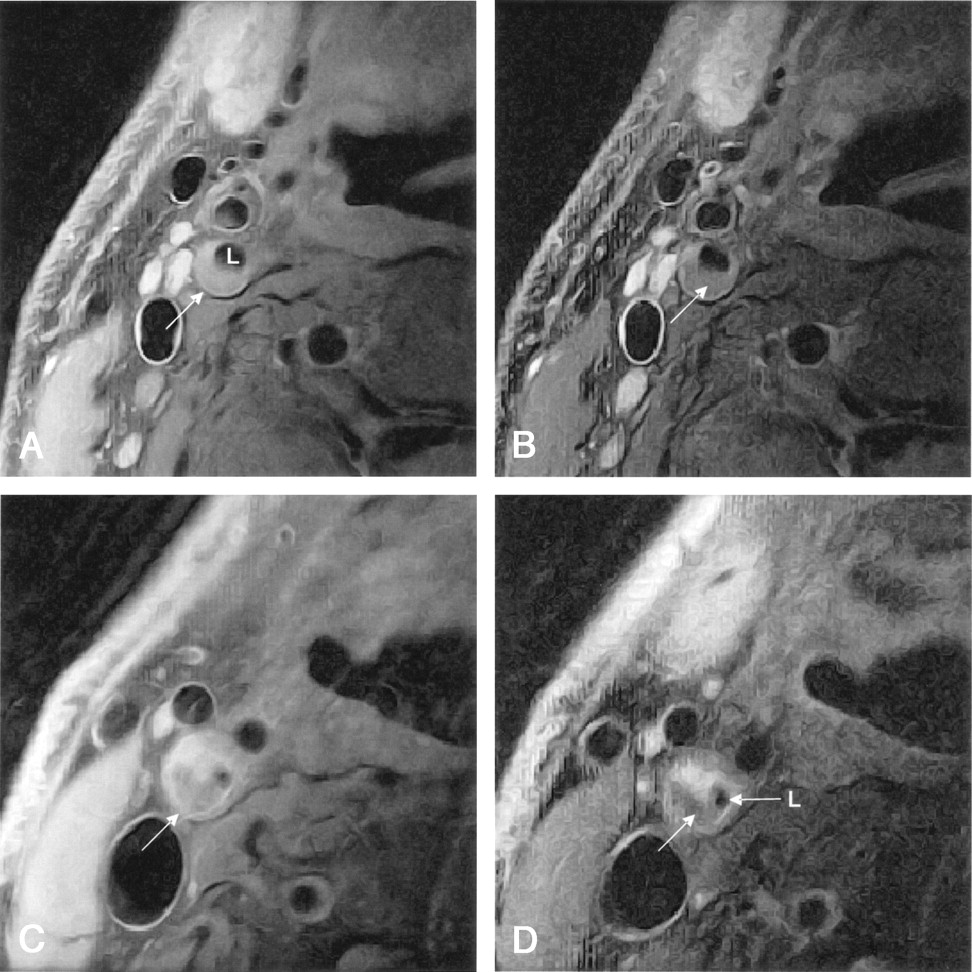

Axial lack-blood fast spin-echo images of the ICA (arrow). Plaque in the ICA is hyperintense. L = lumen.

A and B, Proton density-weighted (A) and corresponding T2-weighted (B) images. Large region of the plaque has intermediate signal intensity, with hyperintense edges.

C and D, Another patient. Proton density-weighted (C) and corresponding T2-weighted (D) images. Plaque in the ICA has a large region of intermediate signal intensity, which is relatively decreased in D, while the rest of the plaque remains hyperintense.